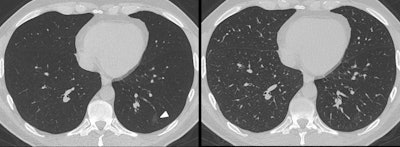

Some studies suggest that chest CT is more sensitive when it comes to diagnosing COVID-19 than reverse transcription polymerase chain reaction (RT-PCR) testing; this sensitivity is due to the modality's ability to identify ground-glass opacity, a key indicator of the disease. But standard transverse CT reconstructions and MPRs can miss ground-glass opacities due to overlay by vascular structures -- and that's bad news for patients, the team wrote.

As MinIP has been shown to have a higher accuracy for assessing GGO in comparison with standard MPRs in interstitial lung disease, Booz and colleagues sought to investigate whether it could improve CT's performance in patients with suspected COVID-19.

Of the 185 patients, 149 (80.5%) had chest CT scans that showed ground-glass opacity. Images processed with MinIP showed higher sensitivity, specificity, and accuracy for evaluating GGO compared with standard MPR series, the group wrote.